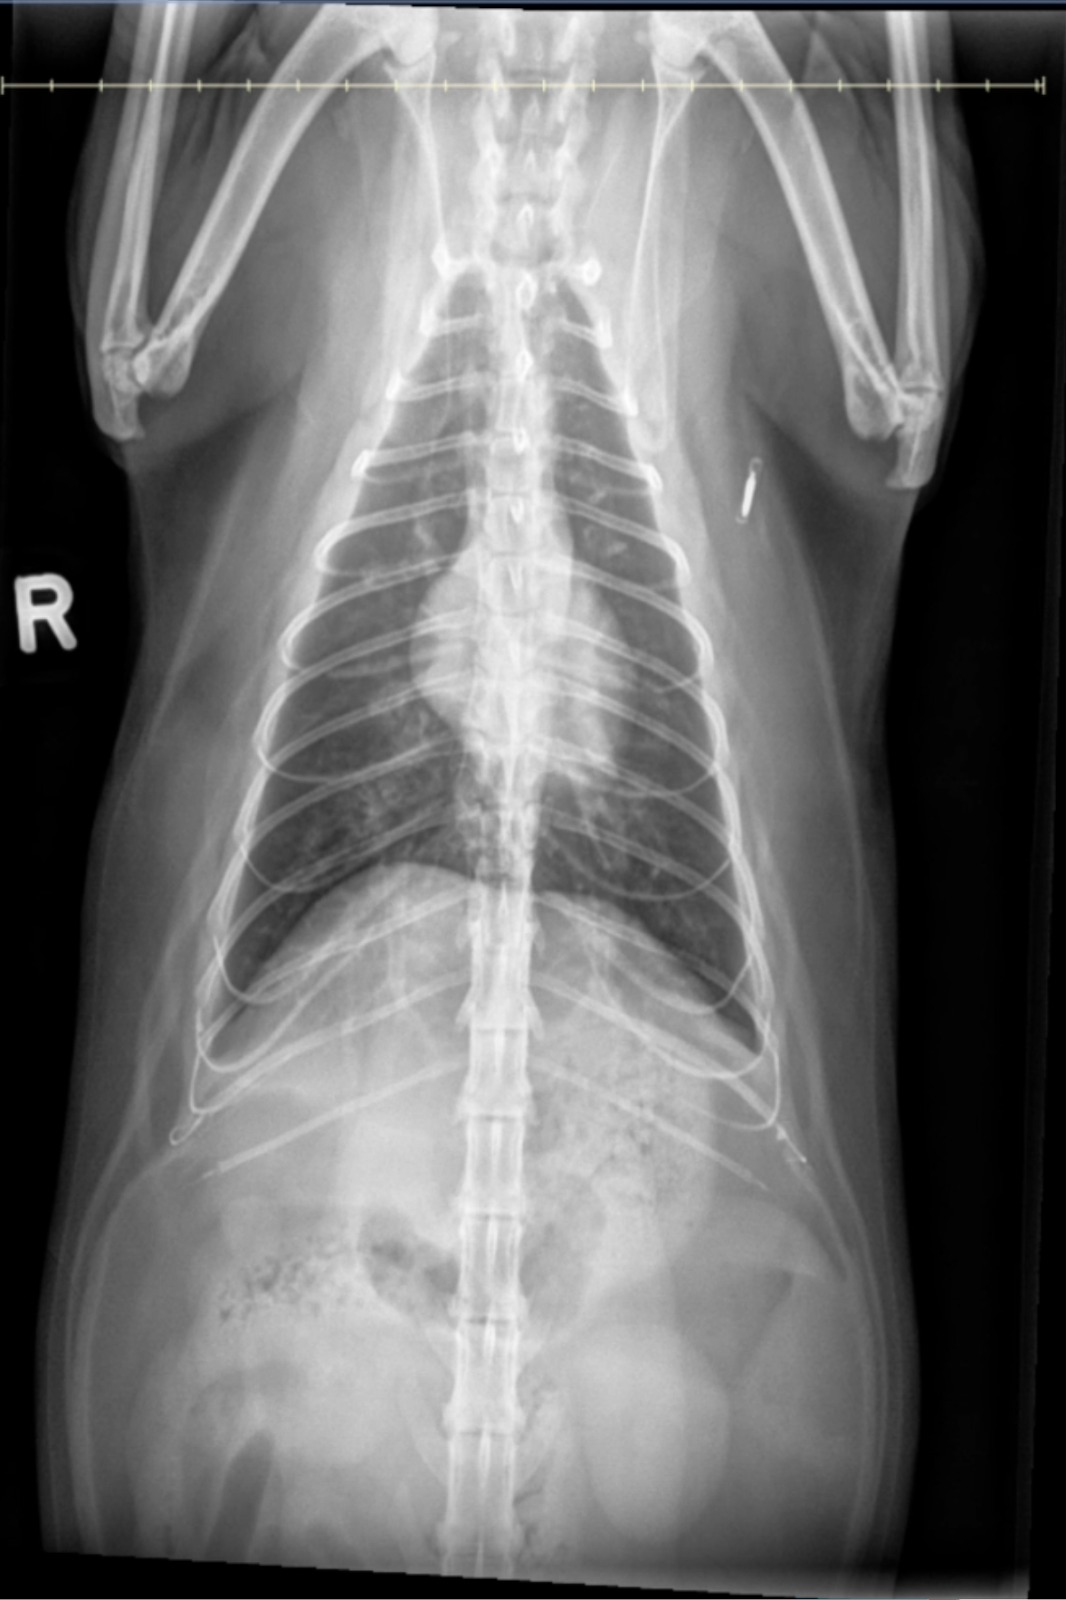

Image 3: Ventrodorsal (VD) View

• Pulmonary Distribution: Bronchial changes are diffuse with no lobar or regional predominance, consistent with a generalized inflammatory process.

• Diaphragmatic Configuration: Mild tenting of the diaphragm is observed, further supporting the presence of air trapping and hyperinflation.

• Other Findings: No pulmonary masses, nodules, focal alveolar consolidations, or pleural effusion are detected.